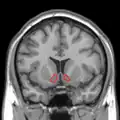

Dopamine and serotonin - MRI coronal slice showing nucleus accumbens outlined in red